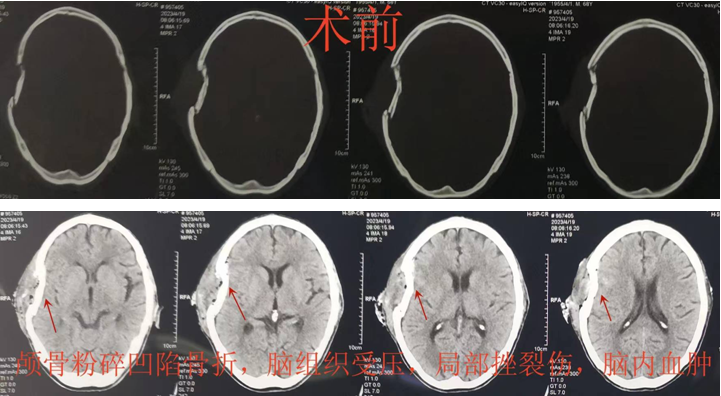

帮扶蒲城县医院的神经外科专家刘晓斌副主任医师,第一时间赶到患者身边进行查看,制订急救方案:患者头皮多处裂伤、颅骨粉碎凹陷骨折,脑组织受压合并挫裂伤等,需要急诊手术解除脑组织压迫,同时考虑到患者高龄,如果去除颅骨,不仅影响后续生活质量,而且二次手术增加创伤风险,并且增加经济负担。刘晓斌副主任医师再三思考,决定行“开颅血肿清除+颅骨粉碎凹陷骨折整复术”。

经过迅速有序的急诊术前准备后,患者被推入手术室,麻醉准备迅速完成,严格头皮裂伤清创后,利用现有的头皮裂伤口个体化设计手术入路,逐层切开头皮,严密止血,完整充分显露颅骨粉碎凹陷骨折,随着骨折片逐一摘取,实际的伤情远比头颅CT片上显示的严重而棘手,骨折的颅骨就像碎裂的玻璃板一样,骨头去除还是保留?去除简单快捷,风险小,也不违反手术原则;然而保留颅骨需要医生付出耐心,同时医疗的责任和压力全部需要术者承担!考虑到患者高龄,也许这次手术是唯一的机会,后续二次颅骨修补手术也许没有条件和机会实施。经过内心激烈的斗争,医者仁心的初心和“弘医弘道”的省医院训给了刘晓斌坚定的信念,经过近2小时认真仔细的操作,原本支离破碎的颅骨被完全整复,患者自体颅骨不仅得到保留,同时避免了二次颅骨修补手术的风险,也极大地节省了医疗费用。手术取得圆满成功,术后患者很快清醒,伤口愈合良好,神经功能恢复顺利,复查头颅CT显示颅骨整复塑型良好。